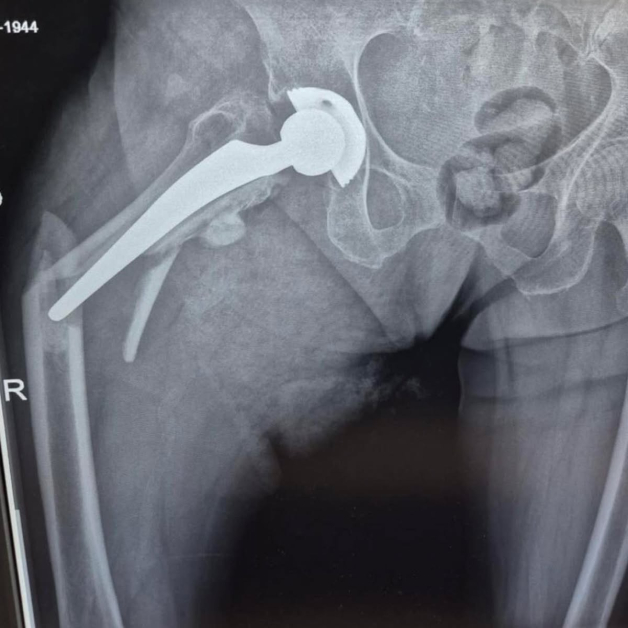

Животът на 80-годишна жена беше избавен след незабавна и сполучлива интервенция в Университетската многопрофилна болница за интензивно лекуване Каспела в Пловдив. Пациентката е с изкуствена тазобедрена става, сложена преди 7 години, само че след рухване е получила съществено строшаване на бедрената кост тъкмо под импланта.

Екипът на болничното заведение, отпред с доктор Димитър Генов и с присъединяване на доктор Благойчо Постоловски, е направил интервенцията бързо и точно. Използвано е особено ревизионно стебло, серклаж и циментна фиксация, с цел да се обезпечи непоклатимост на крайника.

Благодарение на сполучливата намеса, пациентката е могла да се изправи още на идващия ден, с отчасти натоварване на оперирания крайник – нещо извънредно значимо за възобновяване й.